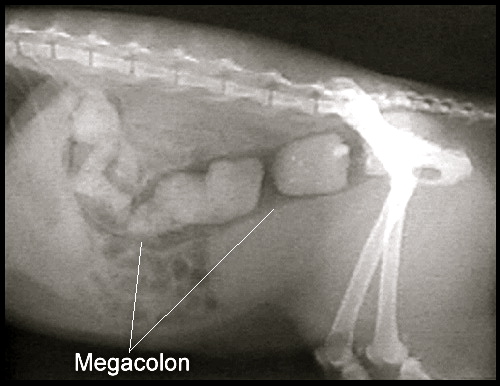

從X光片中可以很清楚地看到糞便堆積在腸子裡